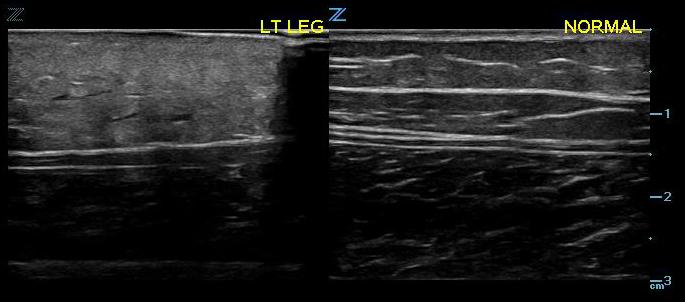

- Figure 3. Early cellulitis vs normal

- The ultrasound appearance of cellulitis will vary depending on its stage and severity. The initial appearance is typically generalized swelling and increased echogenicity of the skin and subcutaneous tissues.2,5

- As cellulitis progresses and the amount of subcutaneous fluid increases, hyperechoic fat lobules become separated by hyperechoic fluid-filled areas. This later stage of cellulitis is most typical and has been described as having a cobblestone appearance.5